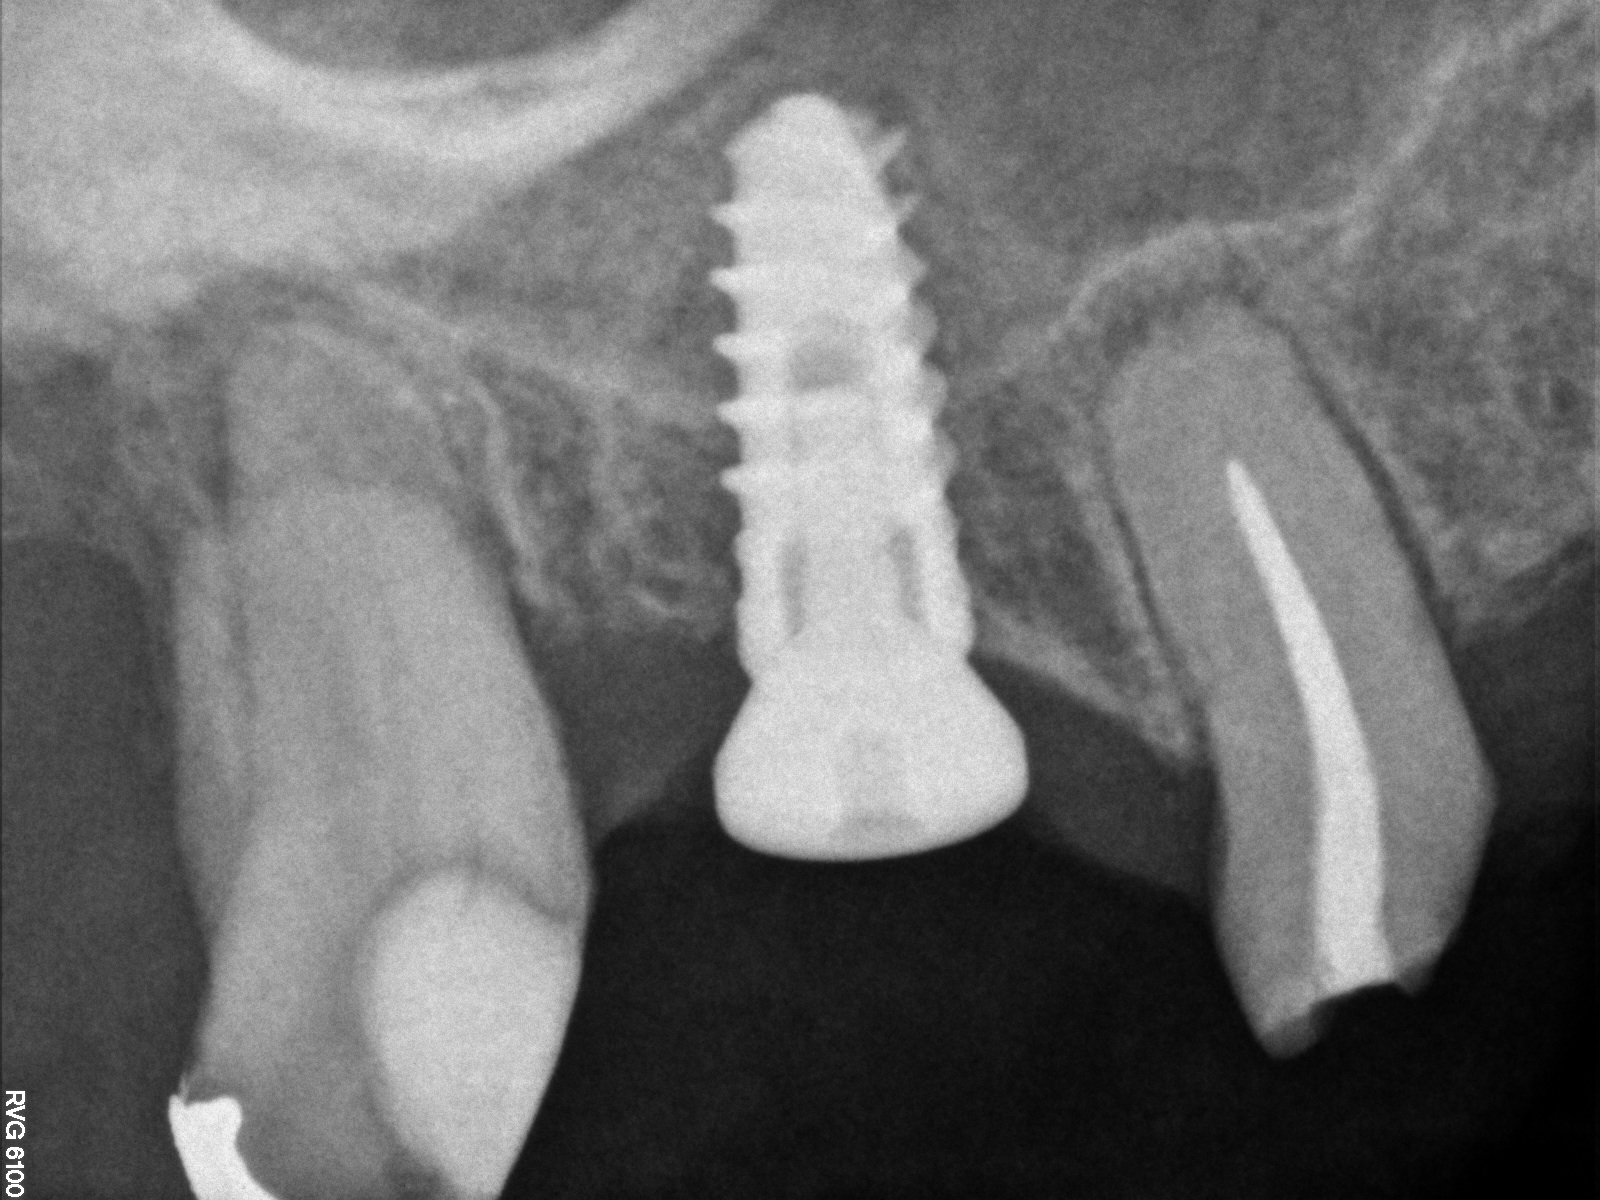

CBCT scan (Kodak 9000D) showing 3.5-month postoperative of implant No. 3 in place. Note homogeneous appearance of the bone.

Fig. 12